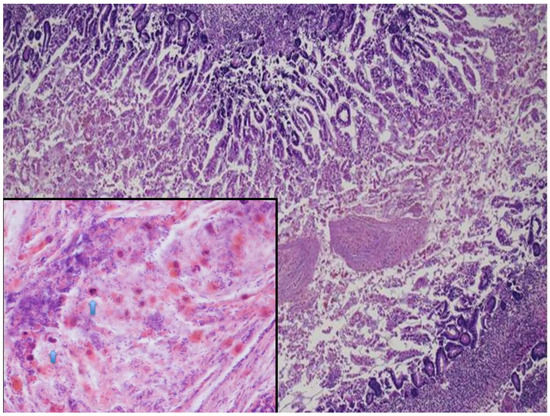

2.2. Fetal Autopsy and Microbiological Results